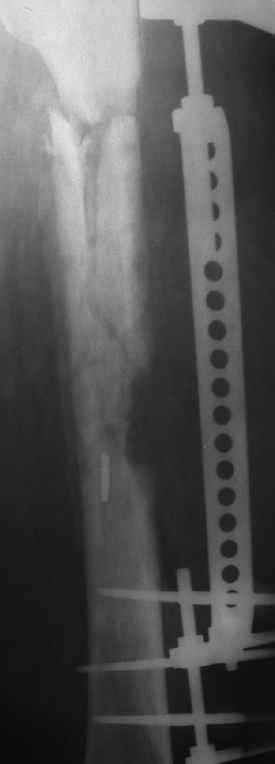

Больной 40лет, поступил 08.06.05г. с закр. оскольчатым переломом бедренной кости в с/3 и в/3 со смещ., 10.06.05г. выполнен остеосинтез LCP

,ч/з 3нед. после операции вскрыта нагноившаяся гематома, промывная система 1нед., через 3-и месяца пластина удалена в связи с инфекцией, секвестрэктомия, ЧКДО. АВФ 8мес.,периодически абсцедирование мягких тканей, санирующие операции, в настоящее время вскрыт абсцесс в с/3 бедра, м/ткани в обл. стержней инфицированы, полость абсцесса сообщается с проксим. и частью дист. стержнейдальнейшая тактика?

Впечатление о секвестрации значительного участка бедренной кости. Если это так, то без удаления секвестров, а фактически создания дефекта не

обойдетесь. Фистулография - значительная секвестрэктомия с краской в свищи -

полноценный дебриджемент - часть стержней удалите, новые для стабилизации введете. При удачной санации будете решать проблему замещения полученного дефекта - наверное по технологии ГА Илизарова. Не удалив "мертвую кость" успеха не ждите. Соответственно современные антибиотики согласно чувствительности и прочая иммуноподдержка не помешает. С ув. А Рыков.

1.Конструкция, находящаяся на бедре, на сегодняшний день ничего, кроме вреда не даёт!

Поэтому я предлагаю Вам её снять, даже если нет сращения. Костные каналы шатающихся стержней рассверлить ручной дрелью, диаметром 7-8 мм.

6. Свежие рентгенснимки без конструкции.